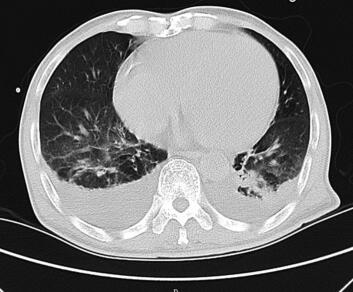

诊治经过:入院后予以吸氧、强心、利尿、抗感染、解痉、平喘、化痰、抗血小板、稳定斑块、营养心肌及改善心肌供血等相应治疗,并给予胺碘酮控制心室率,心室率控制在75~120次/分,气促、胸闷症状得到明显缓解,各项生命体征逐步正常稳定,肺部干湿性啰音逐步减少消失。心脏彩超:左右心房及左心室扩大;左心室弥漫性收缩功能减低;少量二、三尖瓣反流;主动脉瓣退行性变并少量反流;主动脉硬化。肺部CT(图2):双肺纹理增粗、模糊,双肺背侧见大片斑片状渗出及实变影;气道大致通畅,肺门未见明显增大,纵隔内见多发肿大淋巴结。两侧胸腔积液(图1、图3),两下肺膨胀不全。冠状动脉见条形致密影。查血PCT高达84.14ng/ml,入院初始予以头孢哌酮-舒巴坦钠抗感染,PCT逐渐下降,但仍有反复寒战、发热症状,体温波动在37~38℃。直至第4天血培养结果提示金黄色葡萄球菌MRSA(+)。依据药敏试验结果改用环丙沙星和盐酸米诺环素,连续用3天,患者仍有发热、寒战,体温依然波动在37~38℃。遂停用环丙沙星,加用替考拉宁,此后,患者体温明显下降并很快降至正常范围,发热、寒战等症状亦消失。最终病情好转稳定出院。

图3 肺部CT:两侧胸腔积液,两下肺膨胀不全